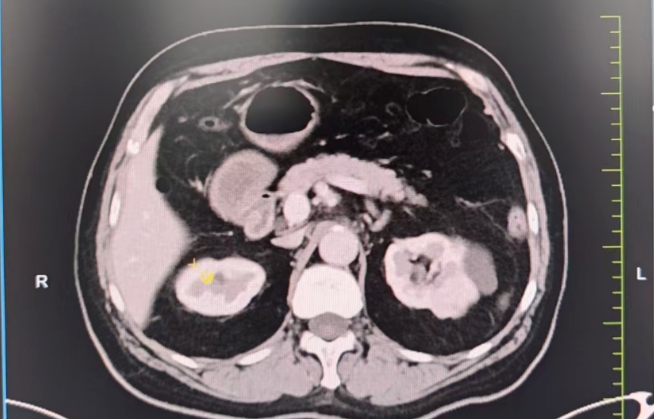

生死抉擇:心臟術后又遇腎腫瘤,求醫(yī)之路一波三折。3年前,劉大爺因嚴重冠心病接受了心臟搭橋手術,并置換主動脈瓣生物瓣。術后長期服用阿司匹林抗凝,病情相對穩(wěn)定。然而半年前,一次體檢發(fā)現(xiàn)他的左腎長出一枚直徑3×2cm的腫瘤,需盡快手術切除。

難題接踵而至 1.保腎難題:劉大爺保腎臟意愿強烈,需行高難度的腹腔鏡腎部分切除術,但因劉大爺心臟術后長期口服阿司匹林抗凝,對于保腎手術增加了出血風險高。2.心臟高風險:多家醫(yī)院評估后認為,劉大爺心臟功能較差(心功能Ⅱ級),術中可能出現(xiàn)心衰、血栓等致命風險,拒絕手術。

兩大難關,精準突破1. 心臟“護航”計劃:由醫(yī)院副院長、心血管中心主任隋立有牽頭,調(diào)整抗凝方案:術前7天停用阿司匹林,改用低分子肝素橋接,降低術中出血風險。優(yōu)化心臟功能:控制血壓,確保心功能穩(wěn)定在Ⅱ級。術中全程心電監(jiān)護,實時調(diào)控血壓、心率,預防心肌缺血。 2. 保腎“微創(chuàng)”方案:泌尿外科團隊在張寶主任的帶領下決定采用后腹腔鏡下腎部分切除術,最大限度保留正常腎組織,術中控制出血量<50ml,手術時間縮短至1.5小時,大幅降低心臟負荷,術后轉入重癥監(jiān)護室(ICU)密切監(jiān)測,24小時專人監(jiān)護心肺功能。